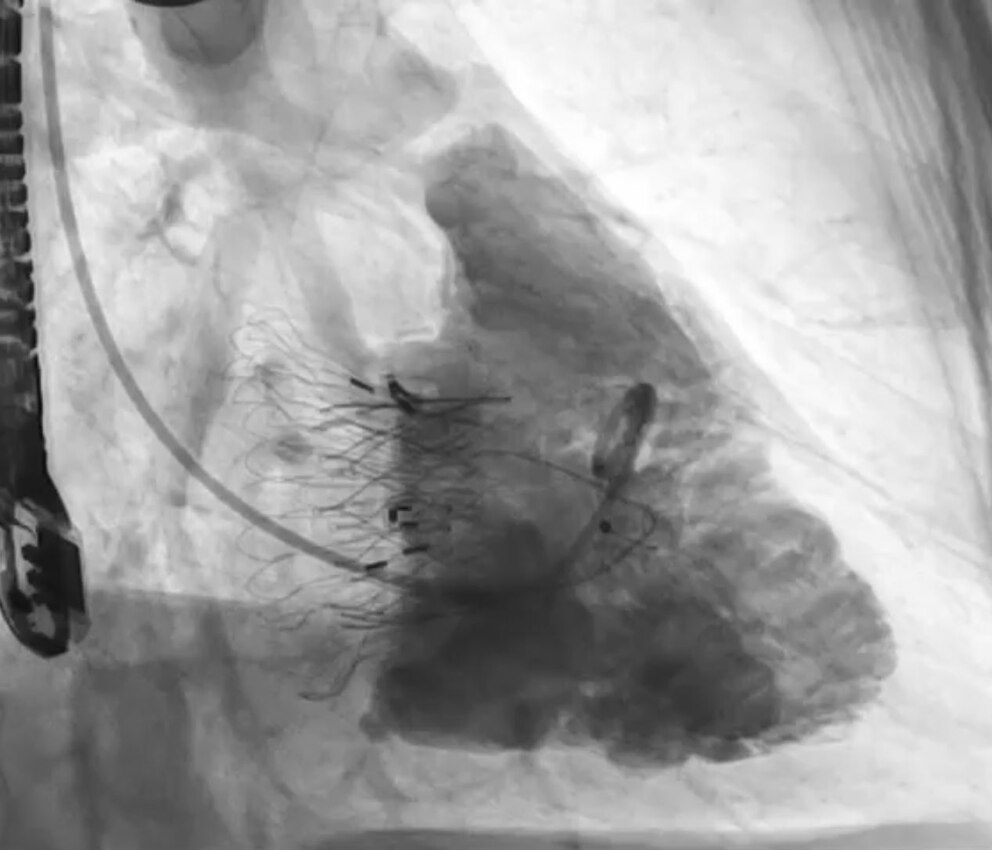

El 6 de junio de 2025, un equipo multidisciplinario del ICBA Instituto Cardiovascular realizó en Argentina la primera intervención de reemplazo valvular tricuspídeo con la técnica LuX-Valve, un procedimiento mínimamente invasivo que representa una alternativa revolucionaria para tratar la insuficiencia tricuspídea severa, una afección subdiagnosticada que afecta especialmente a adultos mayores.

La intervención se llevó a cabo en un paciente con un cuadro complejo, que además padecía un síndrome carcinoide, y fue liderada por los cardiólogos intervencionistas Santiago Ordoñez (MN 148339) y Pablo Spaletra (MN 129332), junto a un equipo de especialistas en imágenes, anestesistas, técnicos y enfermeros. Se trató de la primera vez que este implante, desarrollado en China en 2018 y ya implementado en Europa y Canadá, se utiliza en Sudamérica.

El nuevo procedimiento evita abrir el tórax y detener el corazón, ya que se realiza a través de una pequeña incisión en el cuello. La válvula dañada es reemplazada por un stent valvular que permite mejorar el flujo sanguíneo y aliviar los síntomas. La recuperación es significativamente más rápida y segura, con internaciones promedio de tres a cinco días.